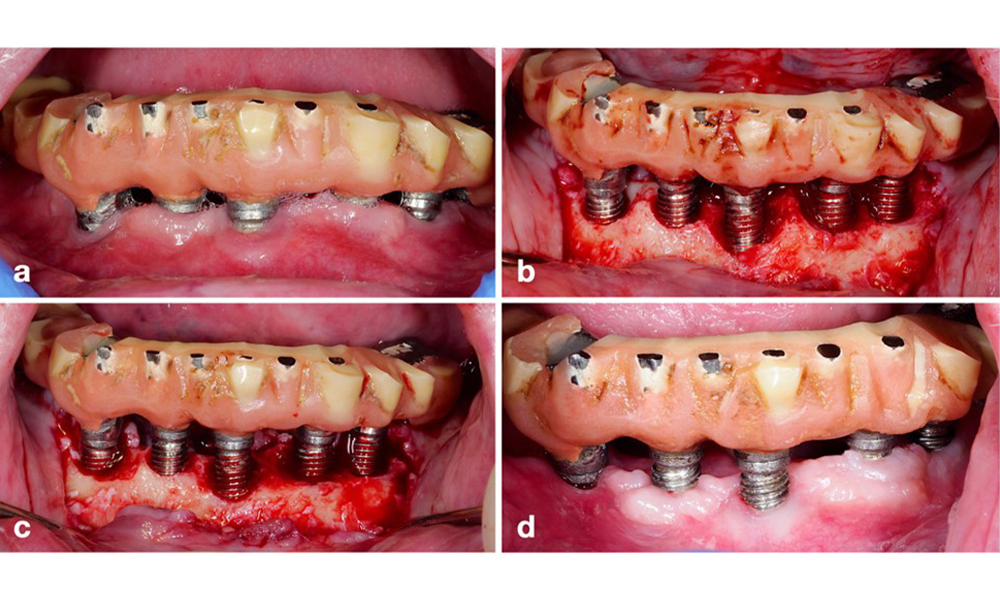

Протетичната реставрация трябва да бъде отстранена както по време на нехирургично, така и по време на хирургично лечение, за да се подобри достъпът до повърхността на импланта. Изборът на хирургична интервенция (напр. резективна, реконструктивна или комбинирана) зависи от няколко фактора: (1) морфология на дефекта (напр. хоризонтална, дехисценция, вътрекостна или комбинирана) (фигура 10), (2) повърхност на импланта ( т.е. обърната или модифицирана/"груба") и (3) наличие или липса на достатъчно кератинизирана и прикрепена лигавица.

Резективен подход (т.е. гингивектомия и/или апикално позиционирано ламбо, с/без реконтуриране на костта) трябва да се избере в случаи с предимно хоризонтална костна загуба или широки дефекти, където потенциалът за костна регенерация е ограничен (фигура 11).

За импланти с модифицирана повърхност и в области, където костната регенерация е малко вероятна, трябва да се обмисли имплантопластика. Тази процедура включва отстраняване на нишките на импланта и изглаждане на микроструктурираната повърхност на импланта с ротиращи инструменти (фигура 12). Този подход улеснява цялостното обеззаразяване на повърхността на импланта и най-важното – подобрява следоперативния контрол на биофилма (Bertl и Stavropoulus 2021; El Chaar et al. 2020; Geremias et al. 2017). Поради липса на достатъчно клинични доказателства има противоречия относно ролята на имплантопластиката (Herrera et al. 2023; Ramanauskaite et al. 2021), но опасенията за предизвикване на възпаление от неизбежното натрупване на титанови частици и повишения риск от фрактура на импланта поради намаляване на здравината му не са доказани (Stavropoulos et al. 2019).

Реконструктивна процедура се препоръчва за импланти с модифицирани повърхности и вътрекостни дефекти, където потенциалът за ре-остеоинтеграция е много по-висок (Monje et al. 2023; Renvert et al. 2009). Това може да включва използването на автогенна кост, костозаместващи материали и/или мембрани (фигура 13) (Donos et al. 2023). Разбира се, реконструктивният подход налага цялостно обеззаразяване на повърхността на импланта. Както лабораторните, така и предклиничните проучвания показват, че пълното отстраняване на биофилма от повърхността на импланта не е възможно (Subramani & Wismeijer 2012). Поради това се препоръчва да се използва комбинация от механични и химични мерки за ефективно обеззаразяване, въпреки че нито един специфичен метод не може да се счита за по-добър (Ramanauskaite et al. 2023; Wilensky et al. 2023). Според няколко лабораторни проучвания устройствата за въздушно полиране са показали по-висока ефективност при отстраняване на биофилм (Francis et al. 2022; Keim et al. 2019, Sahrmann et al., 2015). Въпреки това е важно да се отбележи, че интраоперативната употреба на въздушно полиране не е по предназначение.